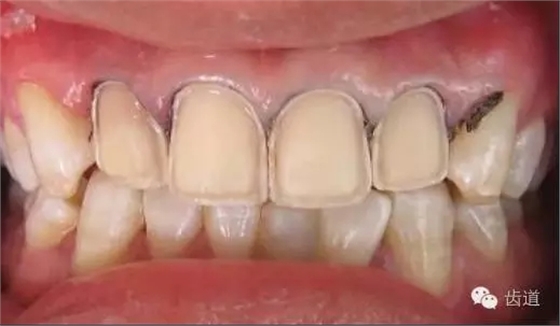

瓷貼面的牙體預(yù)備是影響修復(fù)效果的關(guān)鍵因素之一,適當(dāng)?shù)难荔w預(yù)備可以為瓷貼面提供一定的空間,使修復(fù)后的牙齒外形美觀,患者感覺舒適,利于組織保健。

1、唇面預(yù)備:先用定深車針定出定深溝,再換合適車針磨除剩余的釉質(zhì)。

唇面磨除的量依據(jù)所用貼面材料及牙齒的變色程度而定。

如下圖: